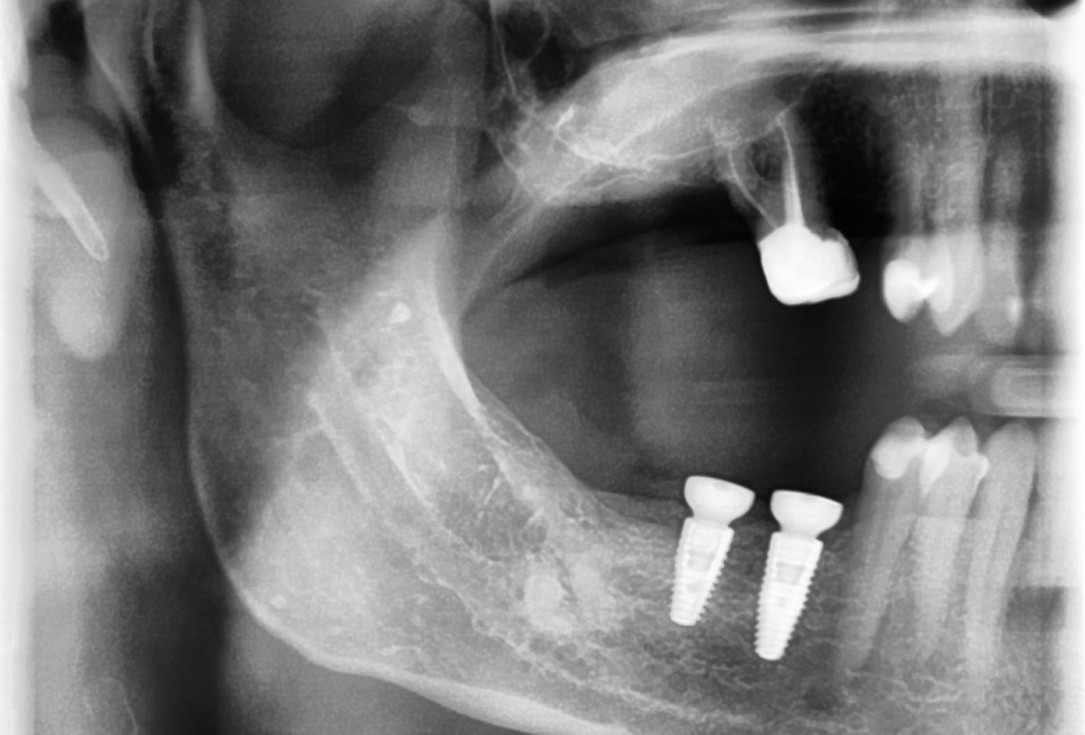

21/28 - X-ray scan of the augmented ridge after implantationThree-dimensional augmentation with maxgraft® cortico - Dr. R. Würdinger

24/28 - X-ray control scan after implant uncovering - excellent and stable osseous situationThree-dimensional augmentation with maxgraft® cortico - Dr. R. Würdinger